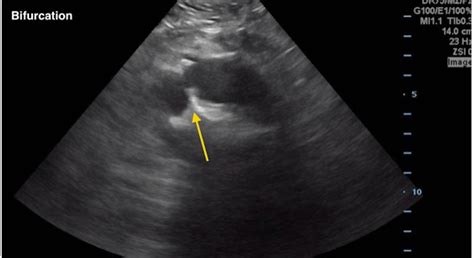

Ultrasound Non-invasive and excellent for initial screening.

Once an Iliac Artery Aneurysm is diagnosed, the treatment plan is usually dictated by the size of the aneurysm and the patient’s overall health. Small, stable aneurysms are often managed through "watchful waiting"—regular ultrasound or CT imaging to monitor for growth.

• iliac artery aneurysm radiology